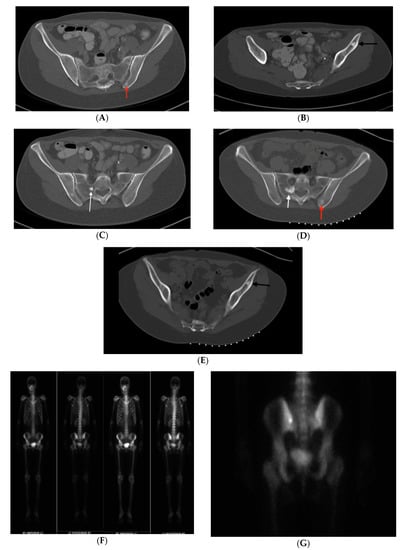

CT demonstrated a radiodense bone lesion with new increased uptake on BS in the left posterior ilium (Figure 4F,G), correlating with the patient’s pain, one stable centrally radiolucent lesion (atypical imaging) in the left anterior ilium (Figure 4B,E) and one enlarged faintly sclerotic lesion in the right sacrum (18 mm) when compared to five years earlier (Figure 4C,D). No BS uptake was seen in the latter two lesions. Mean CT attenuation values for these lesions were 386 HU, 1156 HU and 528 HU respectively.

The presence of left pelvic pain in association with new increased uptake on the BS in the left posterior iliac bone lesion, atypically low CT attenuation values of the left posterior iliac and right sacral lesions and enlargement of the right sacral lesion created an ambiguous clinical picture. For the bone lesion with increased uptake on BS, our differential diagnosis included osteoid osteoma, osteoblastoma, metastatic disease and atypical BI. For the enlarging bone lesion, our differential included atypical enlarging BI, low-grade central osteosarcoma, osteoblastoma and metastatic disease.

In order to clarify the situation, image guided biopsies of the left posterior iliac and right sacral lesions were performed. CT guided needle biopsy of the left posterior ilium lesion revealed woven bone formation with osteoblastic rimming, scattered osteoclasts and loose fibrovascular features consistent with osteoid osteoma (OO). Biopsy of the right sacrum showed dense laminar bone with normal marrow components, confirming a diagnosis of enostosis. The centrally radiolucent lesion in the left anterior ilium was diagnosed clinically as an atypical BI based on radiographic stability, elevated CT attenuation value consistent with BI and absence of uptake on BS. Given the patient’s history of colonic polyposis combined with osteopoikilosis, she was diagnosed with Gardner’s Syndrome. The patient’s OO was subsequently treated with microwave ablation, eliminating her symptoms.

Figure 4. (AI) Case 2. Pelvic axial CT shows enlargement, atypical central radiolucency and osteoid osteoma mimicking BI in a patient with osteopoikilosis. (AC) Initial CT shows a right sacral lesion (white arrow) measuring 8 mm, left anterior iliac centrally radiolucent less sclerotic lesion (black arrow) and sclerotic bone lesion in the left posterior ilium (red arrow) near the SI joint. (D,E) Repeat CT 5-years later shows enlargement to 18 mm in right sacrum (white arrow), stable centrally radiolucent left anterior iliac lesion (black arrow) and left posterior iliac lesion (red arrow) correlating with the patient’s pain, TTP (tenderness to palpation) and increased BS (bone scan) uptake. (F) NM whole body bone scintigraphy demonstrating increased uptake in the left posterior ilium adjacent to the SI joint. (G) Higher magnification emphasizes increased uptake. Given the atypical features, biopsies of the right sacrum (due to enlargement and increased activity on BS) and left posterior ilium (due to pain and local tenderness) were performed. These established the diagnoses of atypical bone island and osteoid osteoma (OO), respectively. Radiofrequency ablation of the OO resolved her symptoms. Left anterior iliac lesion was diagnosed clinically as BI. (H,I) Case 2. Hematoxylin and eosin (H&E) stain of right sacral bone biopsy, establishing a diagnosis of atypical bone island. (H) Magnification 10× (low power view) of the core biopsy showing cortical type bone. (I) Magnification 40× (high power view) of the specimen, displaying lamellar bone with small osteocytes and normal marrow components.